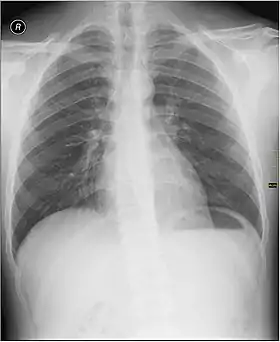

Окремий розділ радіології, Медична радіологія — це медична дисципліна, яка використовує радіологію і медичну візуалізацію для діагностики та лікування захворювань в організмах тварин, включаючи людей.

Для діагностики та лікування захворювань застосовуються різноманітні методи візуалізації, такі як рентгенографія, ультразвук[2], комп'ютерна томографія (КТ), ядерна медицина, включаючи позитронно-емісійну томографію (ПЕТ) та магнітно-резонансну томографію (МРТ)[3]. Інтервенційна радіологія — це виконання зазвичай малоінвазивних медичних процедур з застосуванням технологій візуалізації, згаданих вище.